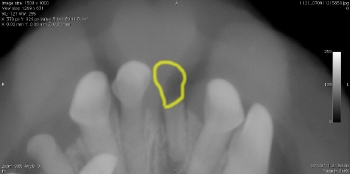

● 歯の破折 4 : 切 歯 の 破 折

真ん中の歯が折れています。

折れた部分を黄色でトレースしています。